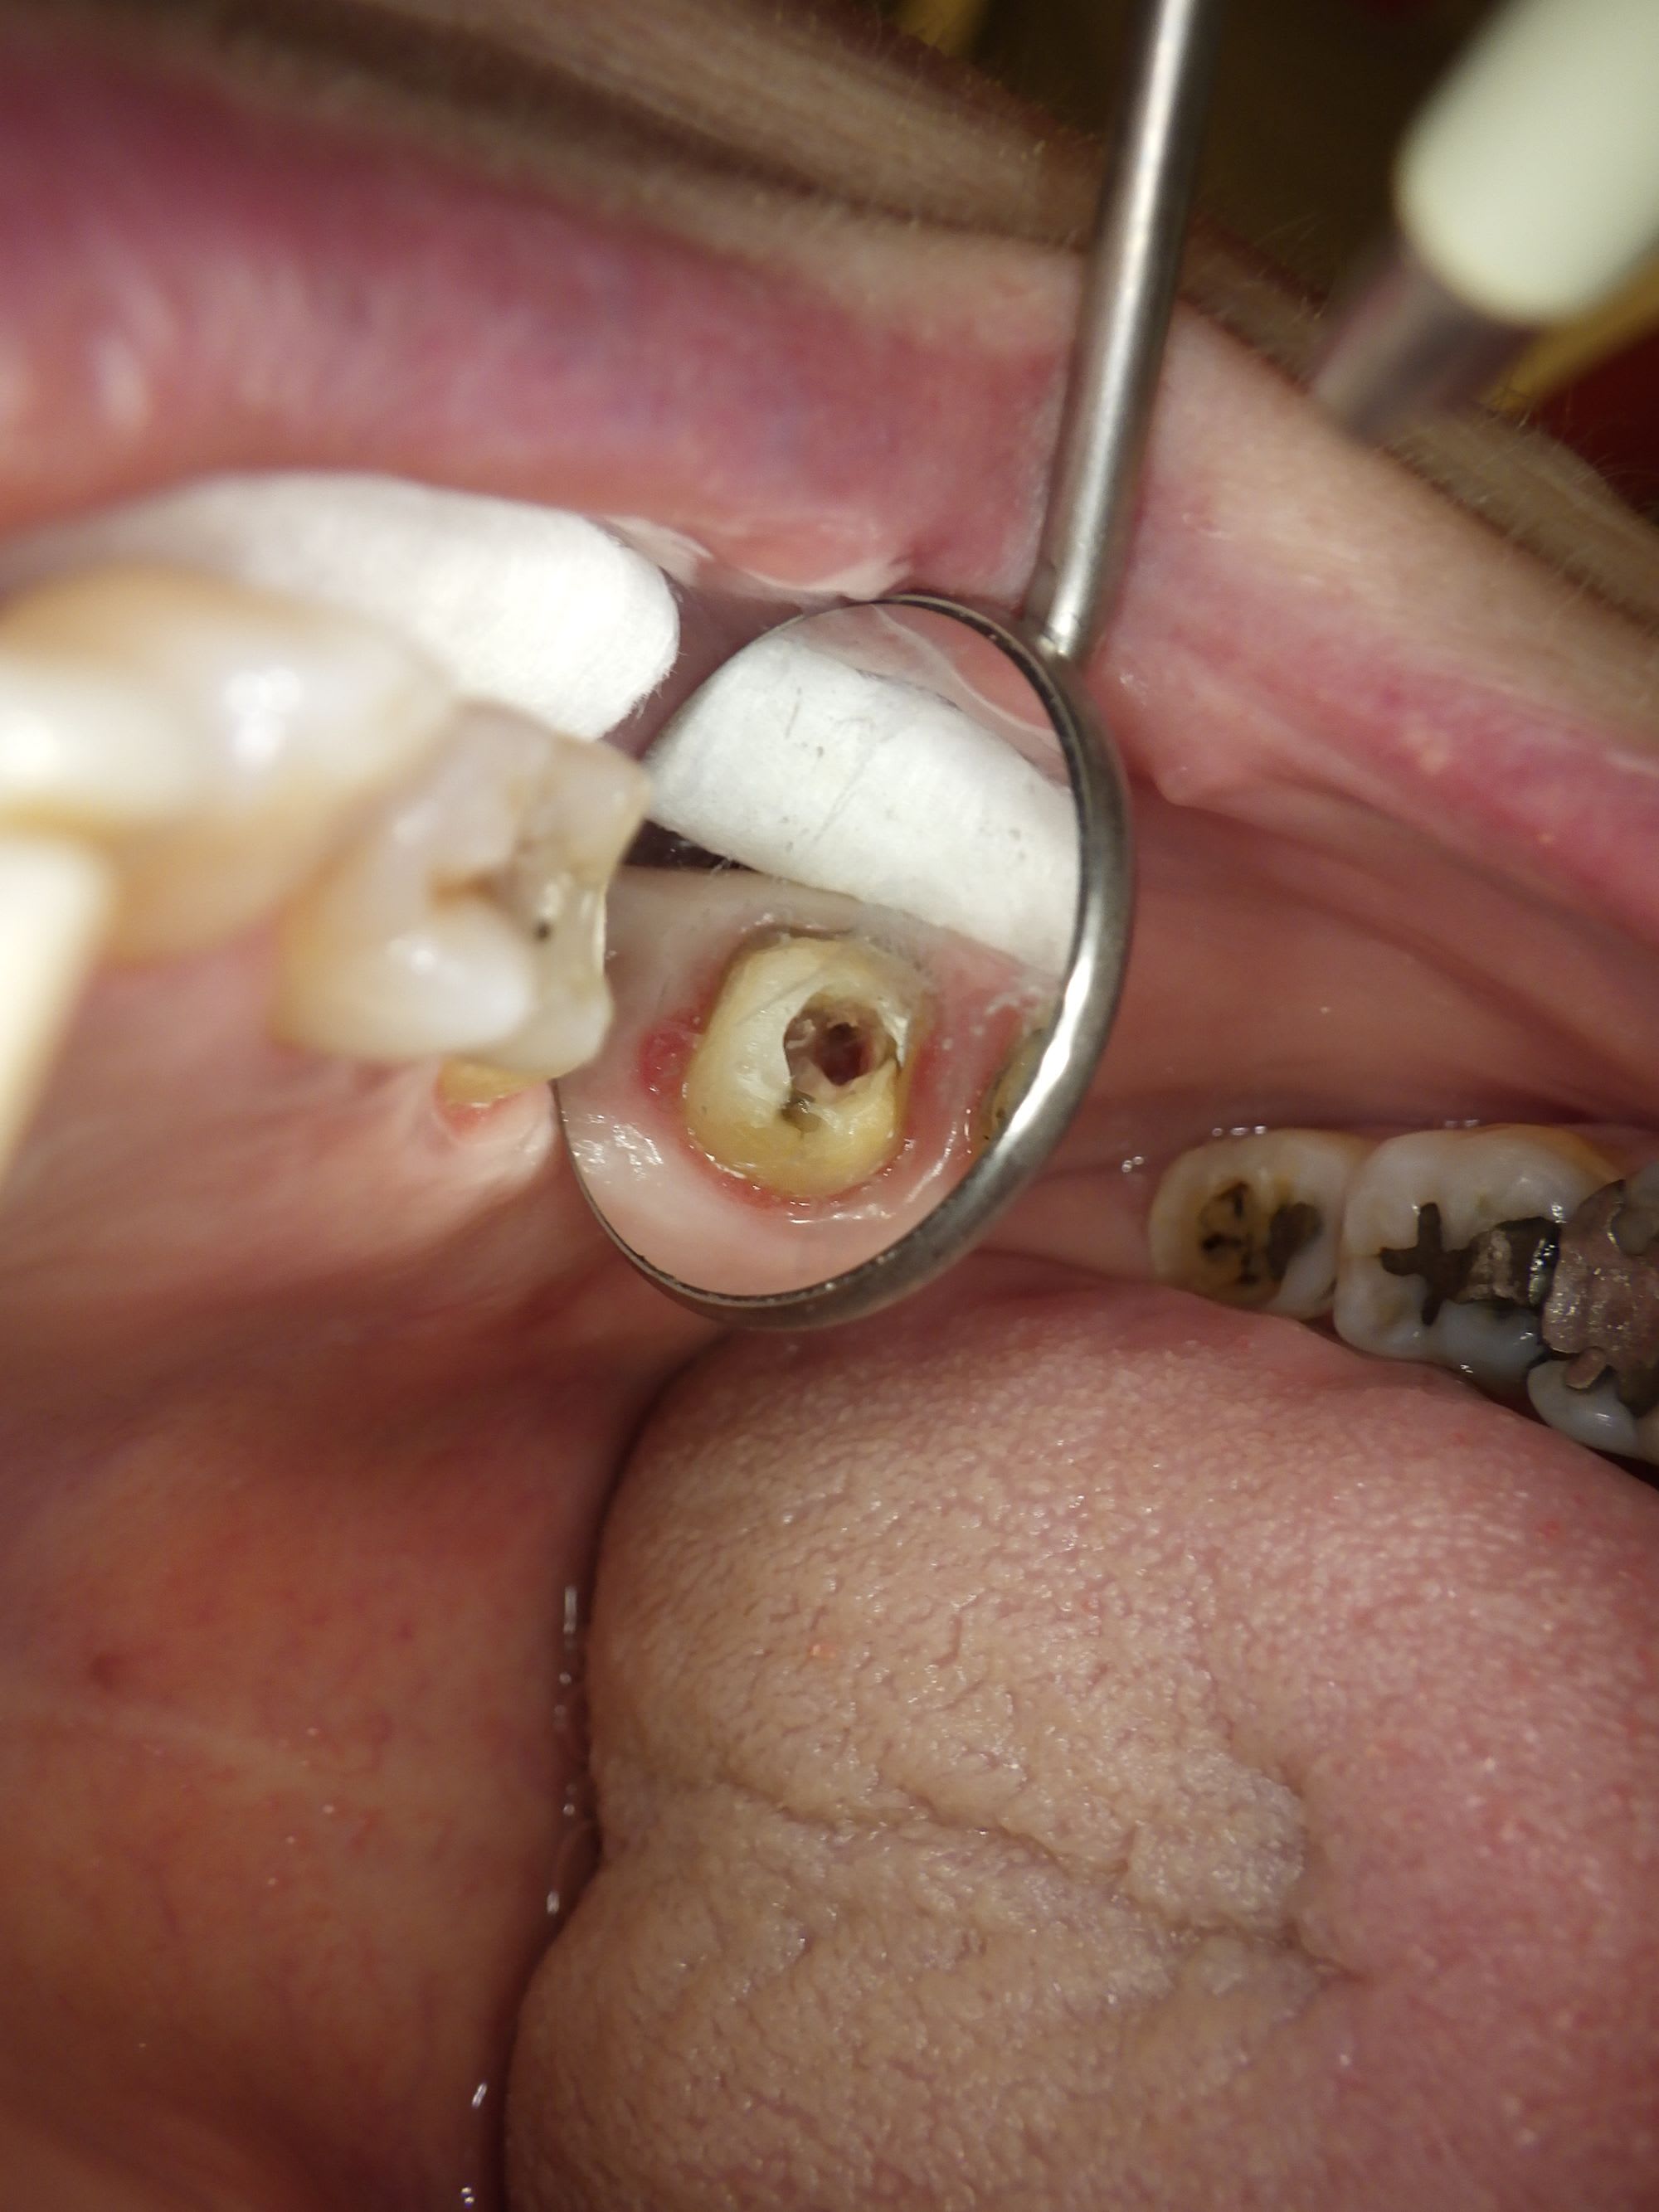

Voici une photo de la chambre , j'ai un peu cherché en palatin et vestibulaire une deuxième entrée, mais il n'y a rien.

Chercher une deuxième entrée en vestibulaire quand on voit sur cette coupe et sur la coupe horizontale que c’est le palatin qui n’est pas obturé, … les mots me manquent.

Pas de digue, c’est la cerise.

C'est bien en palatin que je suis allé cherché ce deuxième canal (cf la photo de la chambre) Je me retrouve très proche de la furcation et je n'ai pas trouvé l'entrée.

Et oui je n'ai pas posé la digue pour ce rendez-vous où j'ai vu la patiente entre 2.

Au dessus tu dis que tu l’as cherché en vestibulaire et palatin : « Voici une photo de la chambre , j'ai un peu cherché en palatin et vestibulaire une deuxième entrée, mais il n'y a rien.«

Le MV2 n’est pas très proche de la furcation mais plutôt plus mésial que le MV1. Il est très visible à la radio et ne doit pas être bien compliqué à traiter, mais pour ça il faut s’en donner les moyens et ça commence par la digue.

@DonChico - Pas le prendre mal, mais je suis surpris que personne n'ai encore critiqué ta cavité d'accès.

L'histoire de l'entrée du canal plus palatin et mésial , c'est ce que je me suis dit aussi en voyant ma photo de la cavité d'accès.

Mais quand je vois à quelle profondeur je suis au niveau de la racine , je me suis dit que je serai retombé sur le canal MV2 sans jouer avec la zone de furcation de la molaire.

C'est toujours stressant d'aller à la pêche dans ces zones là quand il y a une calcification de la chambre.